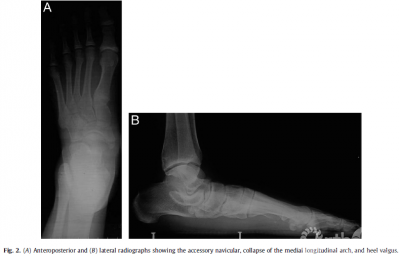

Patients and Methods From December 2008 to July2011, 16 patients (21 feet) with flexible flatfoot,symptomatic AN, and heelvalgus (Fig. 1) underwent MDCO with reconstruction of the PTT on the dorsalnavicular after excision of the AN. All cases were performed by 1 seniorsurgeon at the same hospital. The series consisted of 5 male and 11 female patients,with a mean age of 41.5 years (range 18 to 64years). Of the 16 patients, 11 hadunilateral flatfeet and 5 bilateral flatfeet. All patients had flexibleflatfoot symptoms with a symptomatic AN. The patients presented with chroniclocalized pain on the affected side that made it difficult for them to wearshoes. The presence of flexible flatfoot, AN, and heel valgus were proved radiographically(Fig. 2). Also, T1weighted fat suppressed magnetic resonance imaging showedthat the PTT was abnormally inserted on the AN.

The patients wereevaluated preoperatively, 3, 6, 9, and 12 months postoperatively,and every 6months thereafter by 2 senior surgeons (K.L.T., H.H.C.). The clinical examinationincluded assessment of the American Orthopaedic Foot and Ankle Society (AOFAS)ankle and midfoot scores. The radiologic assessments included evaluation of lateraland anteroposterior weightbearing views of the foot and axial views of theheel.The measurements on the lateral weightbearing radiograph of the footincluded the arch height, assessed as the medial cuneiform height, calcaneusinclination angle,talocalcaneal angle, and talar first metatarsal angle. Thetalocalcaneal angle and talar first metatarsal angle wasmeasured on the anteroposterior view of the weightbearing foot radiograph. Heelvalgus alignment was measured on axial radiographs of the hindfoot. Allprevious measurements and assessments were completed by 2 senior surgeons(K.L.T., H.H.C.). The protocol used to manage foot pain, together with the detailsof any operative or postoperative complications, was recorded.